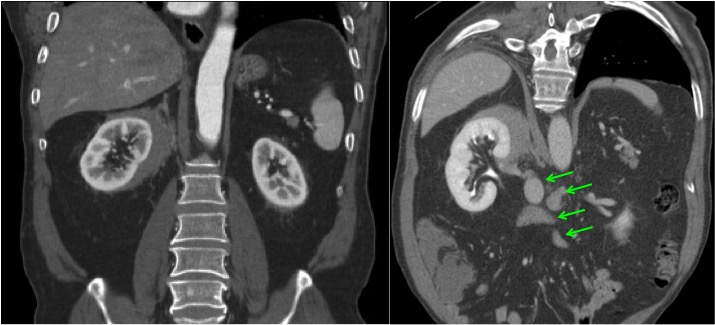

CASO 1: Paciente de 58 años que se realiza TC de abdomen tras historia de dolor abdominal y hematuria microscópica. Refiere pérdida de peso en las últimas semanas.

Estamos ante una afectación bilateral del espacio perirrenal, más evidente en el lado derecho, por masas de densidad de partes blandas en un paciente con numerosas adenopatías retroperitoneales. Estaría indicado realizar una biopsia, ya que el diagnóstico principal orienta hacia un síndrome linfoproliferativo, espcialmente linfoma no Hodgkin tipo B.

2. LINFOMA.

El linfoma renal presenta una gran variedad de manifestaciones. Entre un 3 y un 8 % de linfomas estudiados por TAC tienen afectación renal o perirrenal, más frecuentemente el tipo no Hodgkin.

Patrones de afectación del linfoma renal:

- Multiples masas renales en el riñón (+frecuente)

- Lesión solitaria.

- Adenopatías retroperitoneales con extensión directa a riñón y EPR (nuestro caso de hoy).

- Afectación del espacio perirrenal aislada.

- Infiltración difusa de uno o ambos riñones.

En el caso de que el linfoma afecte al EPR, se ve como una masa homogénea que ocupa este espacio y que desplaza el riñón hacia adelante, ocupando a menudo también el espacio pararrenal anterior. La afectación aislada del EPR por el linfoma es poco frecuente (<10%), es más común la extensión directa desde las adenopatías o grandes conglomerados/masas retroperitoneales (+frec) o la extensión desde el riñón.